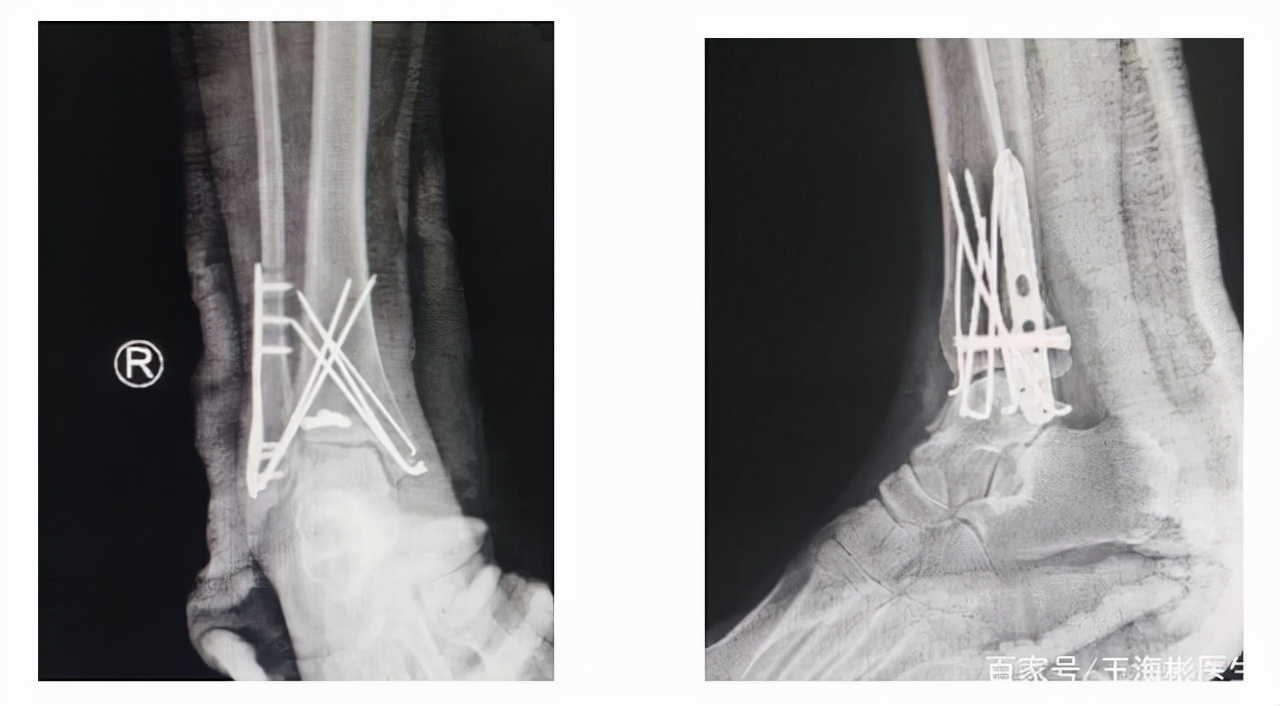

文章所属:王海彬教授团队,插图均来自网络截图(三踝骨折术后片为本院所做)